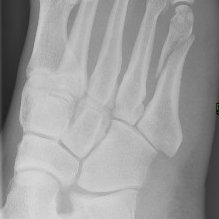

Ho conosciuto la corsa a 35 anni con risultati soddisfacenti, dalla mezza maratona alla 100 km. Dopo 6 anni ho improvvisamente smesso di gareggiare e mi son preso un periodo settennale di transizione. Nel 2005 il richiamo dei fo' di pe e una tranquillità a livello personale, mi portano a riprendere, con ritmi diversi e sensazioni nuove. Non piu' allenamenti massacranti, niente preparazioni mirate e apertura a nuove esperienze. Le gare in montagna entrano nella mia sfera e nel periodo estivo i grandiosi panorami alpini si sostituiscono ai viali alberati delle citta'. Inizio con le skyrace, poi le skymarathon e quindi i trail. Ho calcato tutti i sentieri di montagna, impervi e sconnessi, mi sono aggrappato alle corde nei passaggi pericolosi, ho saltato dalle roccette come un capriolo. Ho concluso skymarathon come il 4 Luglio, le Grigne, la Red Rock, la Dolomites, Zegama, ultratrail come Valdigne, Lavaredo e il Monte Bianco. In quattro anni non ho avuto infortuni e dopo il periodo estivo ho subito iniziato con la strada, ancora mezze, maratone e 100 km. Non mi son mai fermato per traumi o distorsioni e mi son goduto posti ed amici fantastici. La corsa e' quasi diventata un pretesto per fuggire, per evadere, per fare quello che prima era impossibile, economicamente. Programmi sempre a lungo termine, prenotazioni aeree, alberghi, iscrizioni maratone, la salute mi sorregge e non mi tradisce, questo e' quanto gira nel cervello, un tam tam perenne. In fondo e' solo una speranza, non possiamo comandare il nostro fisico, lo possiamo rispettare con adeguate regole di vita. Il periodo e' comunque dei migliori, terminato il Bianco, subito maratone, Berlino, Amsterdam, New York e Reggio alle porte. Bei ricordi che sento finalmente di rendere visibili con delle foto, da appendere in casa. Fatti i quadretti, per meglio posizionarli, utilizzo una sedia ed a piedi scalzi salgo orgoglioso di avere sempre presenti le sensazioni della corsa. Per scendere, un saltello da niente, perdo l'equilibrio ed improvvisamente un tac, dolore e gonfiore al piede. Mi sa ma questa volta la fortuna si e' distratta e le radiografie al pronto soccorso confermano la gravita': frattura scomposta del quinto metatarso. Diagnosi impietosa, gesso e stampelle per 35 giorni, riabilitazione e lento recupero. Addio Reggio e Dubai, lumicino per Siviglia, speranza per Roma e Boston, arrivederci ai trail, compreso il Bianco che ormai avevo deciso di riprovare. La prendo con filosofia, sento comunque che ritornero', la corsa non mi ha mai tradito e continuera' a darmi emozioni e opportunità di conoscere luoghi e persone.       FORVEZETA